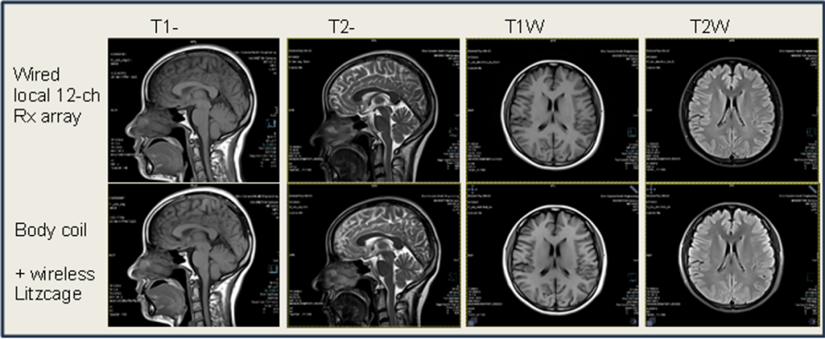

无线线圈与有线线圈对比图

目前,中加健康已完成无线射频线圈产品矩阵搭建,数十套产品能够兼容市场上主流品牌和型号的磁共振成像系统,无需对设备做任何改造即可大幅度增强成像效果,覆盖了头部、颞颌关节、甲状腺、前列腺、盆腔、肝脏、四肢等各个成像部位,产品测试图像获得多位国内医学影像领域临床专家认可,可为我国现有2万多台磁共振设备实现低成本高效率的升级方案。